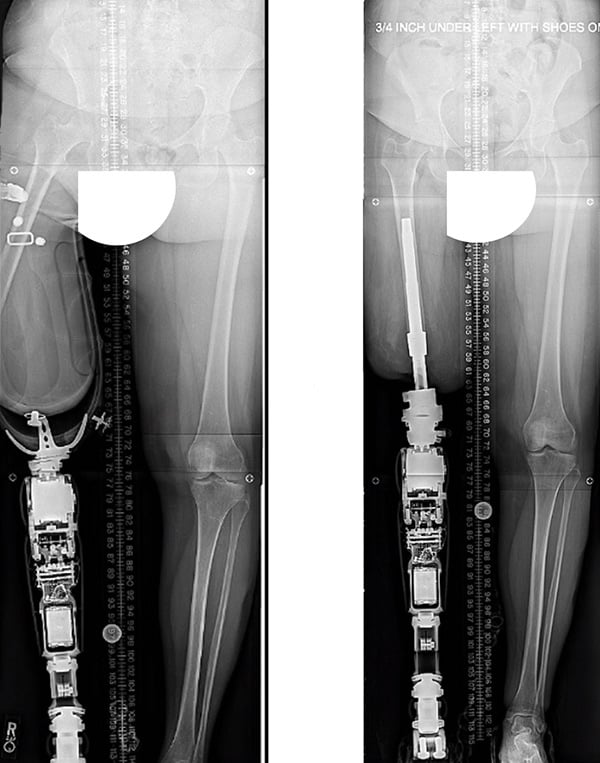

Before-and-after X-ray images showing malalignment between an above-the-knee amputation residual limb with a socket-based prosthesis (left); and an aligned, osseointegrated leg implant and connected prosthesis (right)

In addition, the angle at which the remaining leg bone rests inside the socket is frequently uneven with the prosthetic leg. This is called malalignment. Such awkward angles can cause balance problems and poor energy transfer. This can make it difficult for patients to move well and can even lead to falls and fractures.